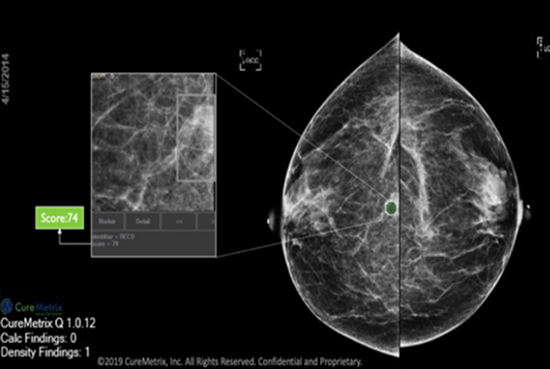

Automatic Reading Drawing Attention on Regions of Interest

cmAssist has the ability to quickly detect key regions of interest on a mammogram, and accurately quantify and label anomalies as suspicious or, instead, verifiably benign. cmAssist does this by searching all the views of a digital 2D-mammogram for abnormal areas of density, mass or calcification and by highlighting suspicious areas requiring further analysis. Once anomalies are flagged in the system, cmAssist then marks the mammogram and highlights the identified anomalies.

Which Patient to Spend More Time on?

The software also generates a unique, data-driven neuScore™ that provides radiologists with a quantitative measure of suspiciousness in a marked region of interest, ranging from 0 (least suspicious) to 100 (highly suspicious). This score can be tracked over time to evaluate the stability or evolution of identified anomalies.